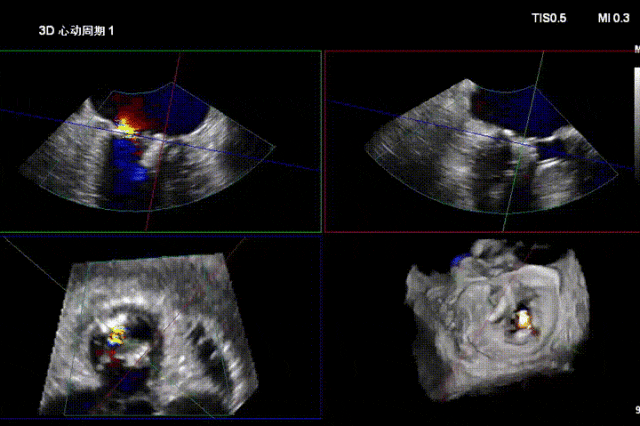

一夹后图像,残余反流位于2区